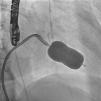

In the procedure, the middle portion of the interatrial septum was punctured (Figure 3) and PMV was performed first by the usual technique with a Mullins sheath and a Brockenbrough needle and inflation of a 26 mm Inoue balloon (Figures 4 and 5), with a good result (absence of transmitral gradient, 2.1 cm2 mitral area and no increase in the degree of valvular regurgitation). Percutaneous LAA closure was then performed. Keeping the guidewire in the same transseptal puncture, a pigtail catheter was introduced into the LAA to allow selective injections into this structure (Figure 6). A 30 mm Amplatzer Cardiac Plug (ACP) (St. Jude Medical), specific for percutaneous LAA closure, was inserted via the ACP release sheath and implanted in the left appendage. It was released successfully and without complications (Figures 7 and 8).